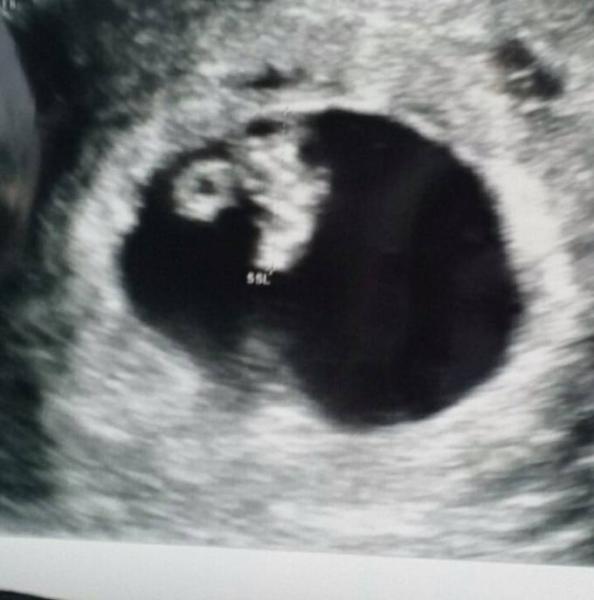

Alles ist gut!!! Baby zeitgerecht zu 7+1 entwickelt, 0,98cm groß. Das Herzchen schlägt und alles ist super.